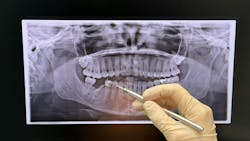

However, the change brought a new handheld unit and sensor. Let’s just say my radiographs were definitely not up to par. I would regularly have cone cuts on the images or have a tricky time placing the new sensor exactly where I wanted it without the patient moving it out of the way with their tongue.

After all these years teaching future dental hygienists how to take radiographs, I had to get used to the unique characteristics of the new machines. But, if you understand the theories behind taking a proper radiograph and know what you’re aiming to see, you’ll get the hang of your new space. Give yourself some grace, be open to support from other team members, and you’ll soon be taking grade A radiographs again.

Lineup the tube head or handheld unit with the teeth and not the ring of XCP. Use the XCP as a guide, not a law. You can help it. Use the holder for support to prevent cone cuts but make sure you’re always having that tube head and teeth parallel to prevent horizontal angulation issues.

Place the sensor as close to where you want him before the patient bites down. Sometimes if we have the sensor not on the tooth when the patient bites, the tongue will move it out of the way. However, if you have it placed exactly where you want it and the holder is touching your target tooth, the sensor won’t move as much when the patient closes.

Don’t be shy to go slow to ensure you’re in the proper area and alignment. It’s better time wise to take a few extra seconds the first time you’re taking images then having to take a retake later on. Plus, this allows for less radiation for the patient.

To review the proper placement of a premolar bitewing, check out this Hygiene Edge video.